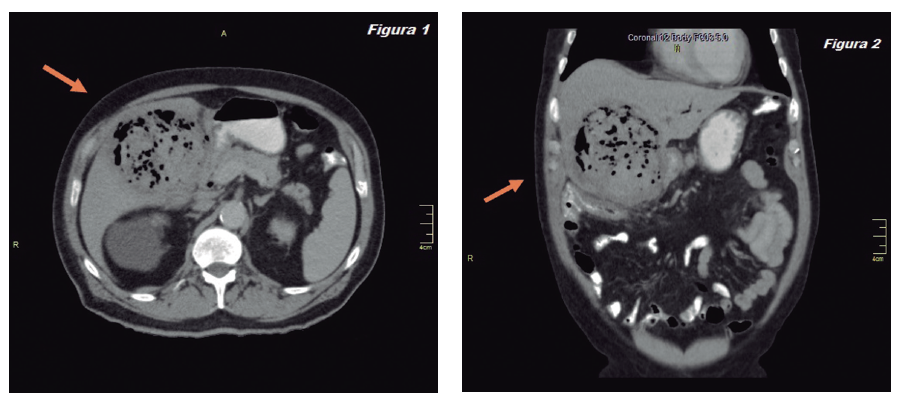

Paciente de 84 años con antecedentes de hipertensión arterial, diabetes mellitus tipo 2, insuficiencia cardíaca y fibrilación auricular, medicado con enalapril, carvedilol, metformina y acenocumarol. Acude al servicio de emergencia de nuestra institución por un cuadro de 24 horas de evolución de dolor abdominal en hipocondrio derecho, fiebre y vómitos. Examen físico: abdomen tenso, doloroso a la palpación en hipocondrio derecho con defensa y reacción peritoneal. Laboratorio: leucocitos 19.000/mm³, plaquetas 205.000/mm³, bilirrubina total: 1,7 mg/dl, bilirrubina directa: 1 mg/dl, TGO: 165 U/L, TGP: 156 U/L, fosfatasa alcalina: 386 U/L, tiempo de protrombina: 35%, KPTT: 15”; el resto sin alteraciones. Ecografía abdominal: vesícula distendida, paredes engrosadas, contenido ecogénico difuso con componente gaseoso que no proyecta sombra acústica posterior. Se efectuó una tomografía computada abdominal (TCA) cuyos hallazgos son motivo de esta presentación (Figuras 1 y 2).